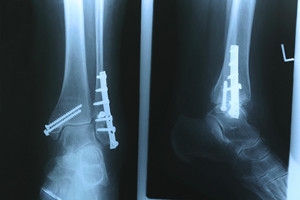

Broken Foot Causes, Symptoms, and Treatment

A broken foot is caused by one of the bones in the foot typically breaking when bended, crushed, or stretched beyond its natural capabilities. Usually the location of the fracture indicates how the break occurred, whether it was through an object, fall, or any other type of injury.

Those that suspect they have a broken foot shoot seek urgent medical attention where a medical professional could diagnose the severity.

Treatment for broken bones varies depending on the cause, severity and location. Some will require the use of splints, casts or crutches while others could even involve surgery to repair the broken bones. Personal care includes the use of ice and keeping the foot stabilized and elevated.

One out of ten broken bones is reported to be in the feet. When an object crushes, bends, or stretches the bone beyond acceptable ranges, bones break. A break in the foot is either a fracture or a straight break.

The location of any break can tell you how the break happened. Toes, for instance, break typically as a result of something being kicked hard and with great force. Heel breaks almost always are a result of an improper landing from a tall height. Twists or sprains are the other two frequent occurrences. As with all usual breaks, they result from unexpected accident or sudden injury. As with stress fractures, breaks form as a process over time from repeated stress on already present cracks. Runners, dancers, and gymnasts are the usual athletes who receive this type of break. Stress fractures result from incredible pressure on the feet. It is no surprise these athletes bear the majority of reported fractures.

Pain, swelling, bruising, and redness are all indicative of the typical symptoms from a broken foot. Severe pain—to the point of not being able to walk—usually depends on the location of the break in the foot. Toes are on the lower scale of pain threshold, but heels are high, as are a few other particular bones. As the severity of the broken foot increases, symptoms like blueness, numbness, misshaping of the foot, cuts, or deformities will become apparent. These symptoms indicate the need to see a medical professional with access to an x-ray facility.

Prior to seeing a specialist, precautions should be taken to reduce pain and swelling. Elevate and stabilize the foot, and refrain from moving it. Immobilization of the foot is the next priority, so creating a homemade splint is acceptable. Keep in mind that while creating a splint, any increase of pain or cutting off blood circulation means that the splint should be removed immediately. Use ice to decrease swelling and relieve pain symptoms.

When dealing with a medical center, the patient should note that the treatment can vary. The treatment will depend on the severity of the fracture and the cause of the break. Crutches, splits, or casts are common treatments while surgery has been known to be used in more severe cases in order to repair the break in the bones.